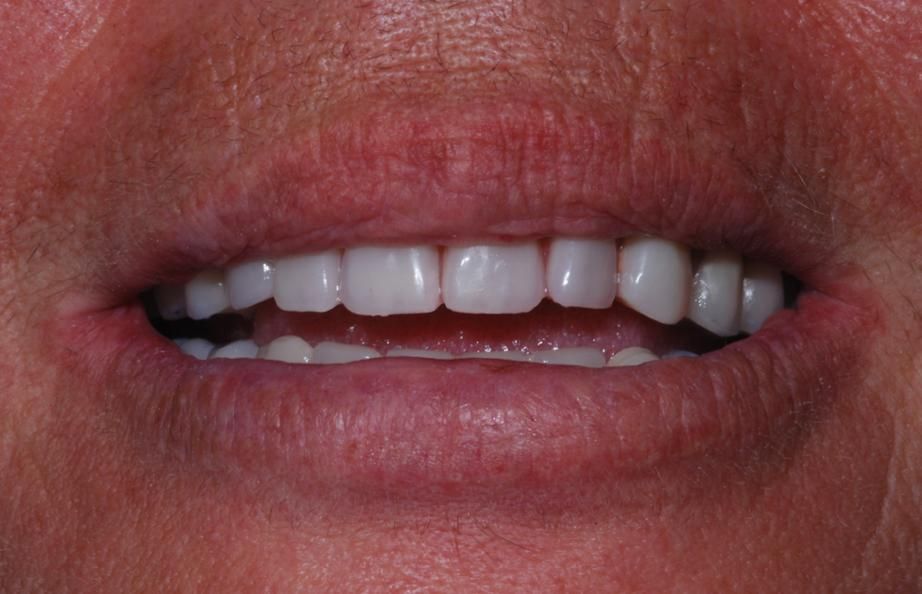

“Maria Giovanna è una signora di 57 anni ma ancora giovane ha perso tutti i denti. È questa una condizione che non permette una vita sociale adeguata e soprattutto vede compromesse la masticazione e la fonazione. Da considerare inoltre il fatto che la mancanza dei denti affossa le labbra e le guance facendo apparire più anziana una persona. La possibilità di entrare in studio senza denti ed uscire con un sorriso da grosse soddisfazioni personali e professionali al medico e al paziente. Maria Giovanna è rinata a nuova vita"

Dopo

Il paziente nella foto, come si può vedere seguendo la linea del tempo è passato da una situazione di mancanza di denti all’inserimento degli impianti e alla protesizzazione del mascellare superiore in un’ora e 15 minuti. Ciò può essere fatto combinando le tecniche della chirurgia guidata e del carico immediato, qualora le condizioni siano idonee.